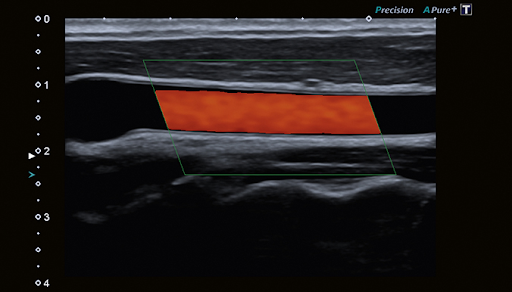

Технологии Precision и Aplipure обеспечивают четкость и детализацию изображений. Эти технологии визуализации предназначены для гармоничной работы, чтобы каждое изображение обеспечивало максимально возможный уровень клинической информации для быстрой и точной диагностики.

Ряд инструментов для исследования сосудов, включая цветовой доплер, ADF и регистрацию пульсовой волны, облегчают работу врача.